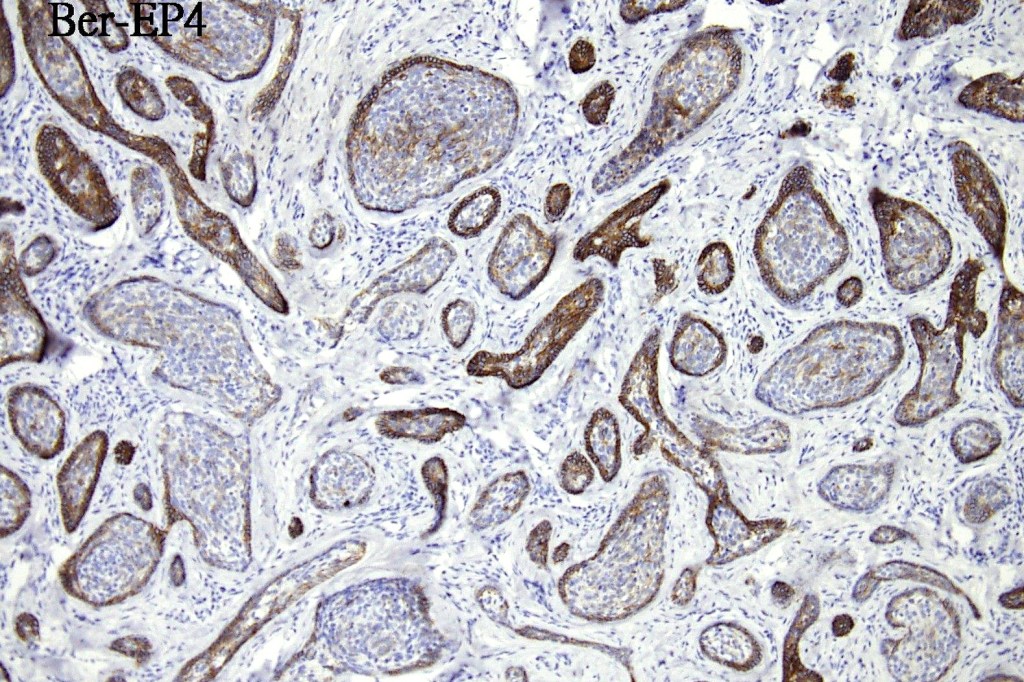

•Keratin & EMA +ve, CEA –ve

•Bcl-2 +ve peripheral epithelial layer, BerEP4 peripheral epithelial layer layer

.Stromal CD10 & CD34